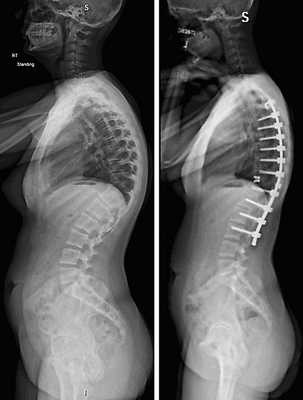

Коррекция кифоза грудного отдела.